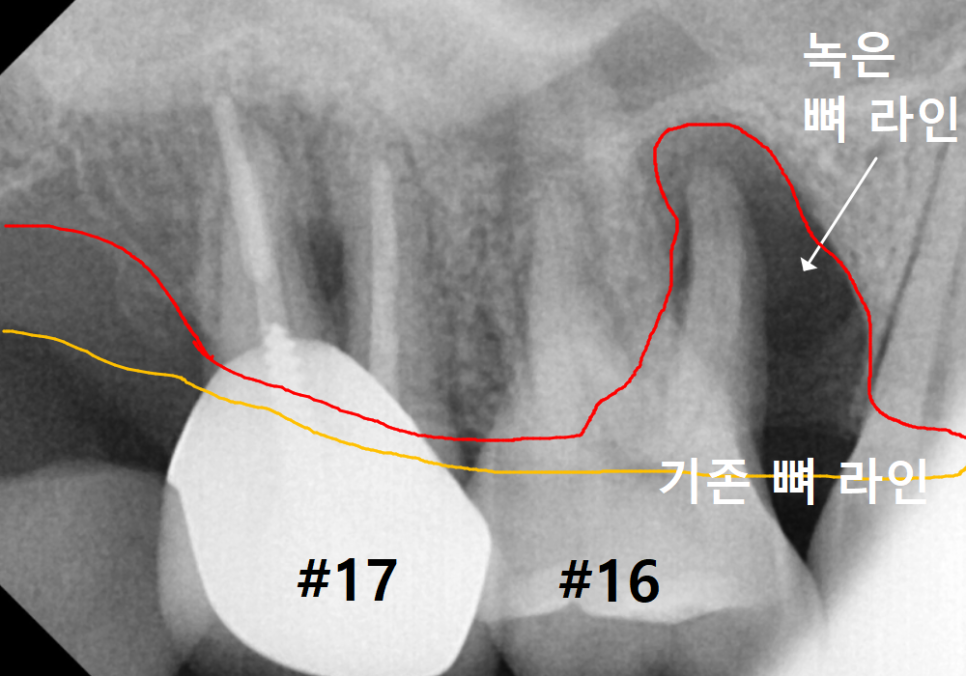

CT로 확인해 보니 뒷니(#17) 역시

뼈가 이만큼이나 녹아 있었습니다.

240327

앞에 치아와 비교해도 손색없을 정도로

뼈가 많이 사라진 상태였죠.

분명 파노라마 사진에서는

괜찮아 보였는데,

왜 CT에서는 이렇게 뼈가 녹은 게

확실히 보일까요?

그 이유는 파노라마는 1차원적인 평면 사진이라

상이 하나로 겹쳐 보일 수 있기 때문입니다.

반면 3D CT는 입체적인 사진이라

치아를 앞뒤 옆으로 돌려볼 수 있어

훨씬 자세하고 정확한 진단이 가능하죠.

정밀 진단 결과, 안타깝게도

두 치아(#16,17) 모두 발치를 피할 수 없었습니다.

하지만 더 큰 문제는

임플란트를 심을 공간이었죠.

보통 임플란트가 저작력을 버티려면

최소 7~8mm 이상의 뼈 길이가 필요한데,

환자분의 남은 뼈 두께는

고작 2.9mm였습니다.